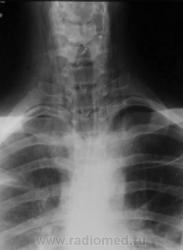

Молодой человек получил удар в шею. Был доставлен в травмпункт, дан барий для исключения перфорации пищевода.

Перфорации похоже нет, но есть другое...

Это чем же его ударили? Я так понимаю, ограниченный пневмоторакс слева  + эмфизема мягких тканей шеи?

Шейный кифоз настораживает.Отсутствие легочного рисунка в верхней доле левого легкого с краем легкогоЭмфизема мягких тканей шеи..Согласна с коллегой.Пару лет назад по кифозу ШОП, увеличению превертебрального пространства и столбу воздуха поставили разрыв пищевода.Дали  контраст-подтвердили.

Затекания контраста за пределы пищевода на представленных рентгенограммах не выявлено. Нет фазы тугого заполнения. Левосторонний пневмоторакс.

Да, ЛОРа 100% надо на консультацию, т.к. барий затек не туда.